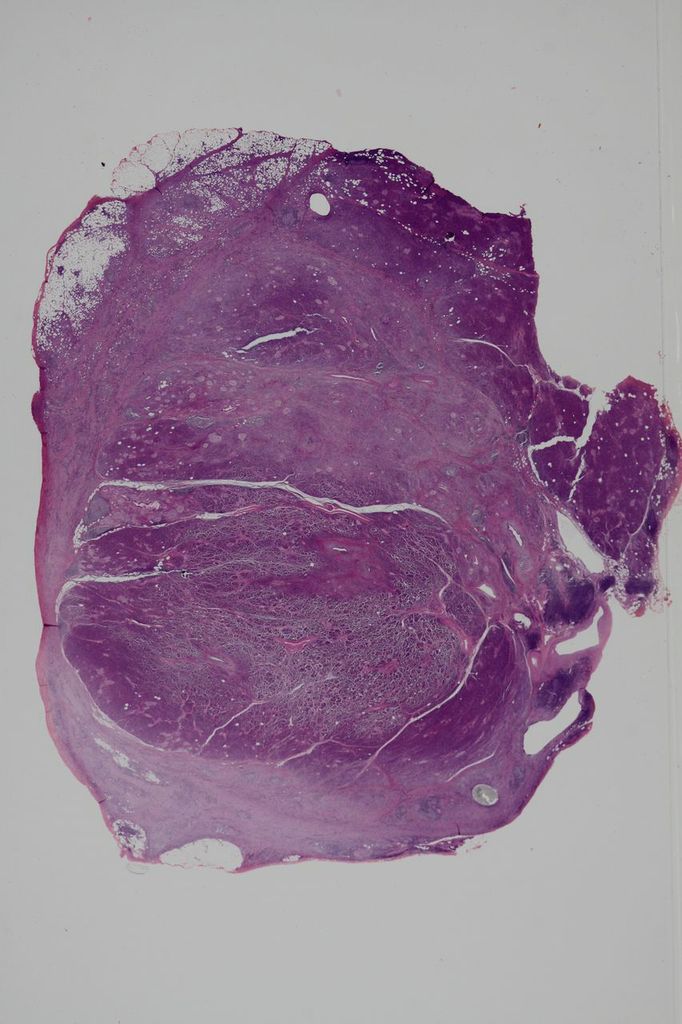

Macroscopically, the affected pancreas is usually enlarged. The lesion can be diffuse or focal, but focal lesions are particularly prone to be resected because of the clinical difficulty in distinguishing them from pancreatic cancer. The pancreatic lobules are relatively well preserved (Figure 1), but focal destruction is not uncommon. The pancreatic duct system is open despite imaging findings suggestive of stenosis. The pancreatic parenchyma is often surrounded by a sheath of inflammation involving the peripheral parenchyma and peripancreatic adipose tissue. This feature corresponds to the radiological finding of a “capsule-like rim”.

Figure 1. Macroscopic features of type 1 AIP. A portion of the pancreas is surrounded by a sheath of inflammation (white arrows). Pancreatic lobular structure is well preserved. The main pancreatic duct (blue arrow) is open, and is involved by the fibroinflammatory lession ("thickened duct wall").